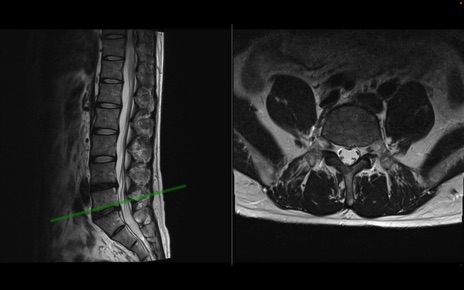

【整形】TIPS症例1 腰椎MRI 横断像と矢状断像

【症例】40歳代男性

【主訴】左臀部〜大腿後面痛み

【現病歴】2週間前から腰痛あり。2日前に夜中にくしゃみをした際に激痛が出現。疼痛強いため来院。

【身体所見】左臀部〜大腿後面、下腿後面のしびれ。SLR -/+ 30度、うつ伏せ困難、筋力低下なし。

異常所見と診断は?